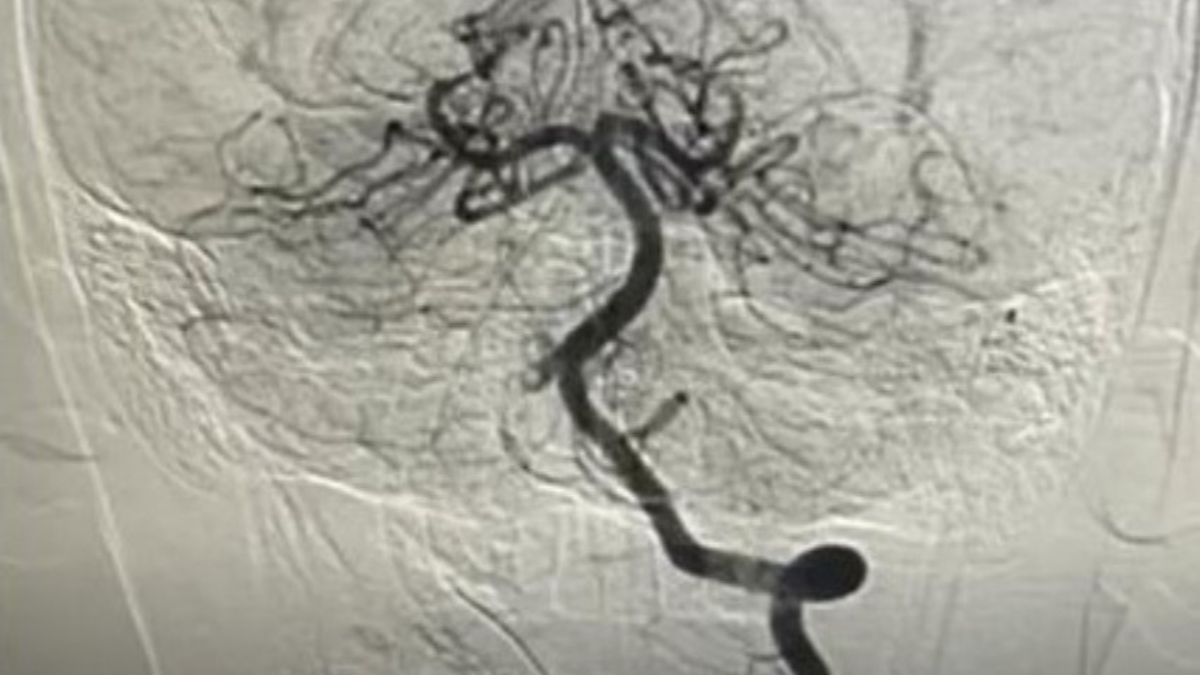

Kết quả chụp MRI não và cột sống cổ cho thấy trẻ bị nhồi máu não cấp vùng hành não – một dạng đột quỵ do thiếu máu não. Hình ảnh mạch máu ghi nhận huyết khối gần như gây tắc hoàn toàn động mạch đốt sống phải, đe dọa tổn thương não nặng nếu không được tái thông kịp thời. Các bác sĩ đã hội chẩn khẩn và quyết định chụp mạch số hóa xóa nền để đánh giá chính xác vị trí, mức độ tắc nghẽn trước khi can thiệp.

Hình ảnh chụp mạch máu xóa nền DSA

Bác sĩ chuyên khoa II Trần Công Bảo Phụng cùng ê-kíp đã tiến hành can thiệp nội mạch cấp cứu. Ống thông được luồn từ động mạch đùi lên đến động mạch đốt sống phải, kết hợp bơm thuốc tiêu sợi huyết tại chỗ và sử dụng dụng cụ chuyên dụng để lấy huyết khối. Sau thủ thuật, dòng máu lên não được tái lập hoàn toàn. Bệnh nhi tỉnh táo, sinh hiệu ổn định và được chuyển về hồi sức theo dõi. Sau khoảng một tuần điều trị và tập phục hồi chức năng, trẻ có thể vận động gần như bình thường.